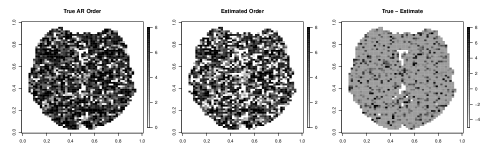

Our motivating example comes from a single subject in a fMRI experiment examining a face-repetition stimulus. The experiment involves the presentation of either famous faces (F) or non-famous faces (N) with each type of face presented two times. Convolving this experiment design with the canonical hemodynamic response function and its time and dispersion derivatives leads to a design matrix with twelve columns plus one extra column for an intercept term in the regression model. After performing the necessary pre-processing steps as described in Penny et al. (2005), we fit a simple linear regression at each of the voxels. After obtaining the residuals from each voxel-specific fit, we fit an AR process up to order for each voxel using the “ar” function in R. We then selected the optimal AR orders based on the AIC criterion. Figure 1 displays a pictoral representation of the results.

Figure 1 shows considerable variablity in the estimated AR order across voxels. While most of the estimated optimal AR orders are 4 or less, higher orders up to are selected at some of the voxels. Furthermore, these estimated AR orders tend to show some extent of spatial clustering. If, as is often done, we simply model the data using a homogeneous low-order AR process, then the voxels with higher order estimated AR orders would be incorrectly modeled, and this inaccuracy in the modeling of temporal noise will have an impact on the inference on the covariates of interest (via underestimated standard errors), resulting in potentially false inferences about brain activation. To address this issue, we propose a spatially varying autoregressive order (SVARO) model, where the AR orders vary spatially across the brain. This is made possible by adopting a spike-and-slab prior with a stochastic search variable selection scheme. Spatial clustering of AR orders is incorporated by imposing an Ising prior (Ising, 1925) as the latent indicator for the spike and slab prior. We update the latent indicators using the Swendsen-Wang algorithm (Swendsen and Wang, 1987) alternating with Gibbs sampling in our MCMC algorithm. To prevent the phase transition problem associated with the Ising model, we derive theoretical bounds as in Li et al. (2015) and use these bounds to prevent critical slowing of the algorithm. We compare our model with the GLM-AR model of Penny et al. (2007) (implemented under two schemes: our self written MCMC sampler and the VB algorithm available in the SPM software) in terms of mean squared error (MSE) and sensitivity. We conduct these comparisons using two simulation studies and then compare results on the motivating data set.